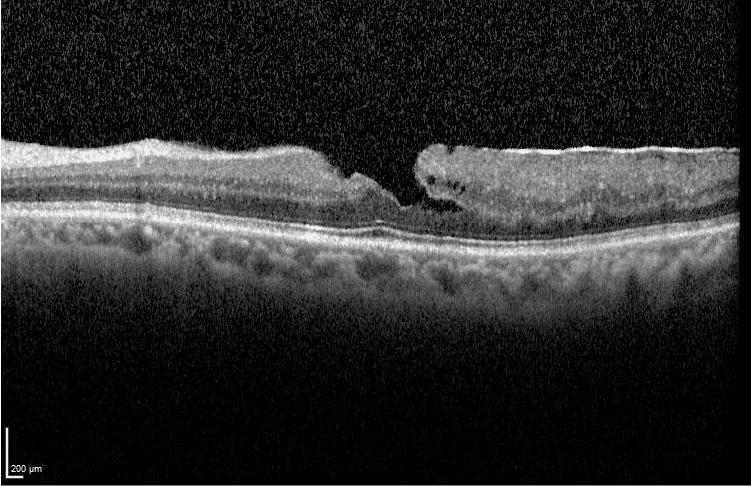

Agujeros maculares lamelares

Las capas de la retina están más afectadas que la visión. Pueden estar relacionados con membranas epirretinianas.

Agujero macular lamelar